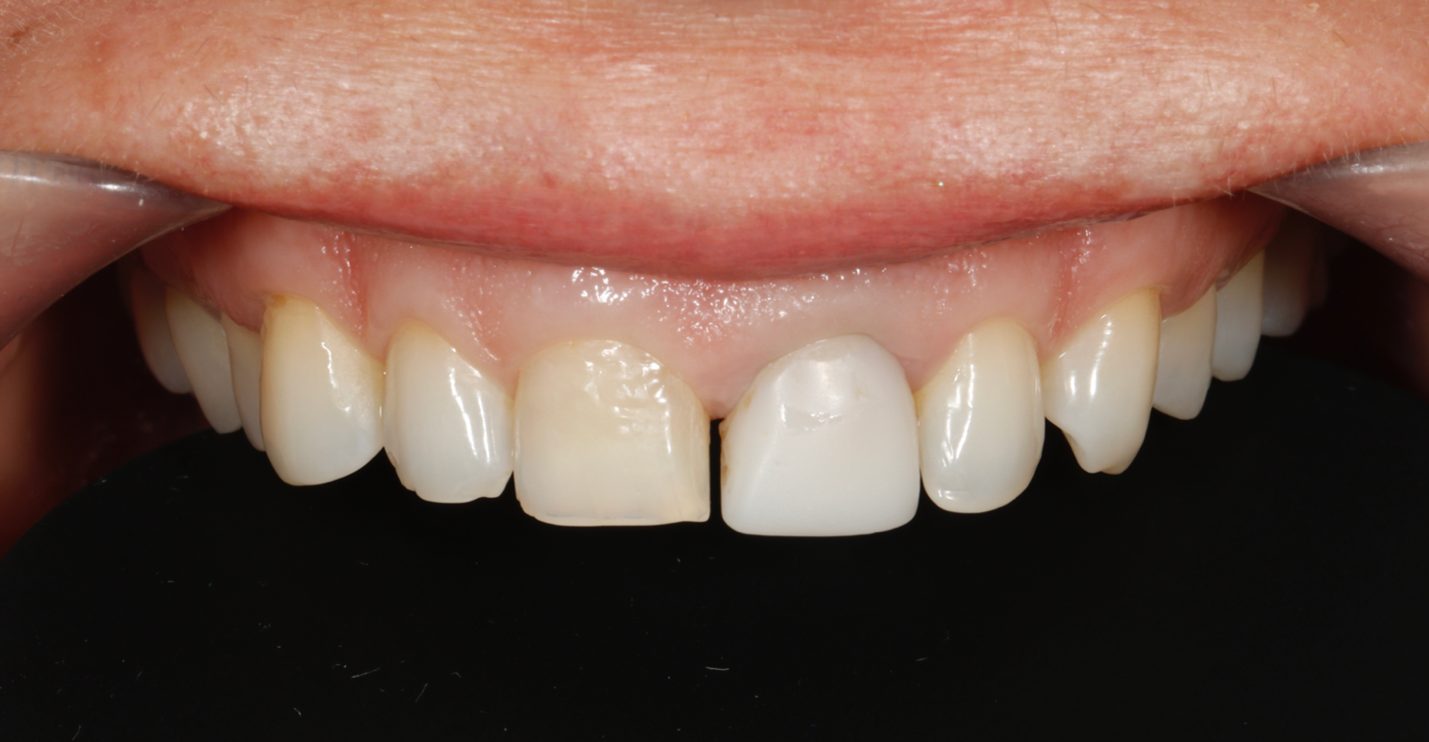

Пациентка И., 43 лет, обратилась в клинику с жалобами на эстетику передних зубов (рис. 1). Зуб 21 ранее проходил эндодонтическое лечение более шести лет назад. На момент первичного осмотра зуб был восстановлен временной композитной коронкой. Зуб 11 имел более тёмный оттенок по сравнению с верхними боковыми резцами. После обсуждения плана лечения пациентка выбрала восстановление зубов с 13 по 23 с использованием керамических реставраций.

Рис. 1. A – вид передней группы зубов с ретракторами. Зуб 21 ранее был пролечен эндодонтически и восстановлен временной коронкой.

B – улыбка пациента.